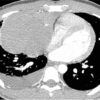

1. U quái lành tính

– Kích thước lớn 3-25cm. Tỷ trọng hỗn hợp, gồm các thành phần:

+ Thành phần nang (90%): 1 hoặc nhiều ổ, thành dày 1-5mm lát bởi tế bào biểu mô tiết chầy nhầy, có thể có vách, sau tiêm ngấm thuốc viền và vách. Các nang lông, tuyến da, cơ và thành phần mô mềm nằm trong nang.

+ Thành phần chất béo (76%): có thể tạo mức dịch-mỡ (10%)

+ Thành phần mô mềm: đồng nhất, ngấm thuốc sau tiêm.

+ Vôi hóa (53%): thường hình vành khăn, có thể thấy vôi hóa hình răng và xương (26%).

– U quái chưa trưởng thành thường chỉ có thành phần đặc.

– Khi có biến chứng vỡ tỷ trọng các thành phần không đồng nhất.2. U tế bào mầm ác tính

– Thành phần đặc chiếm ưu thế, mỡ (40%).

– Hoại tử, chảy máu, ít vôi hóa.

– Ngấm thuốc không đều sau tiêm.

– Biểu hiện di căn: xâm lấn thành ngực, màng phổi, màng tim, hạch vùng, di căn xa.V. Phân biệt